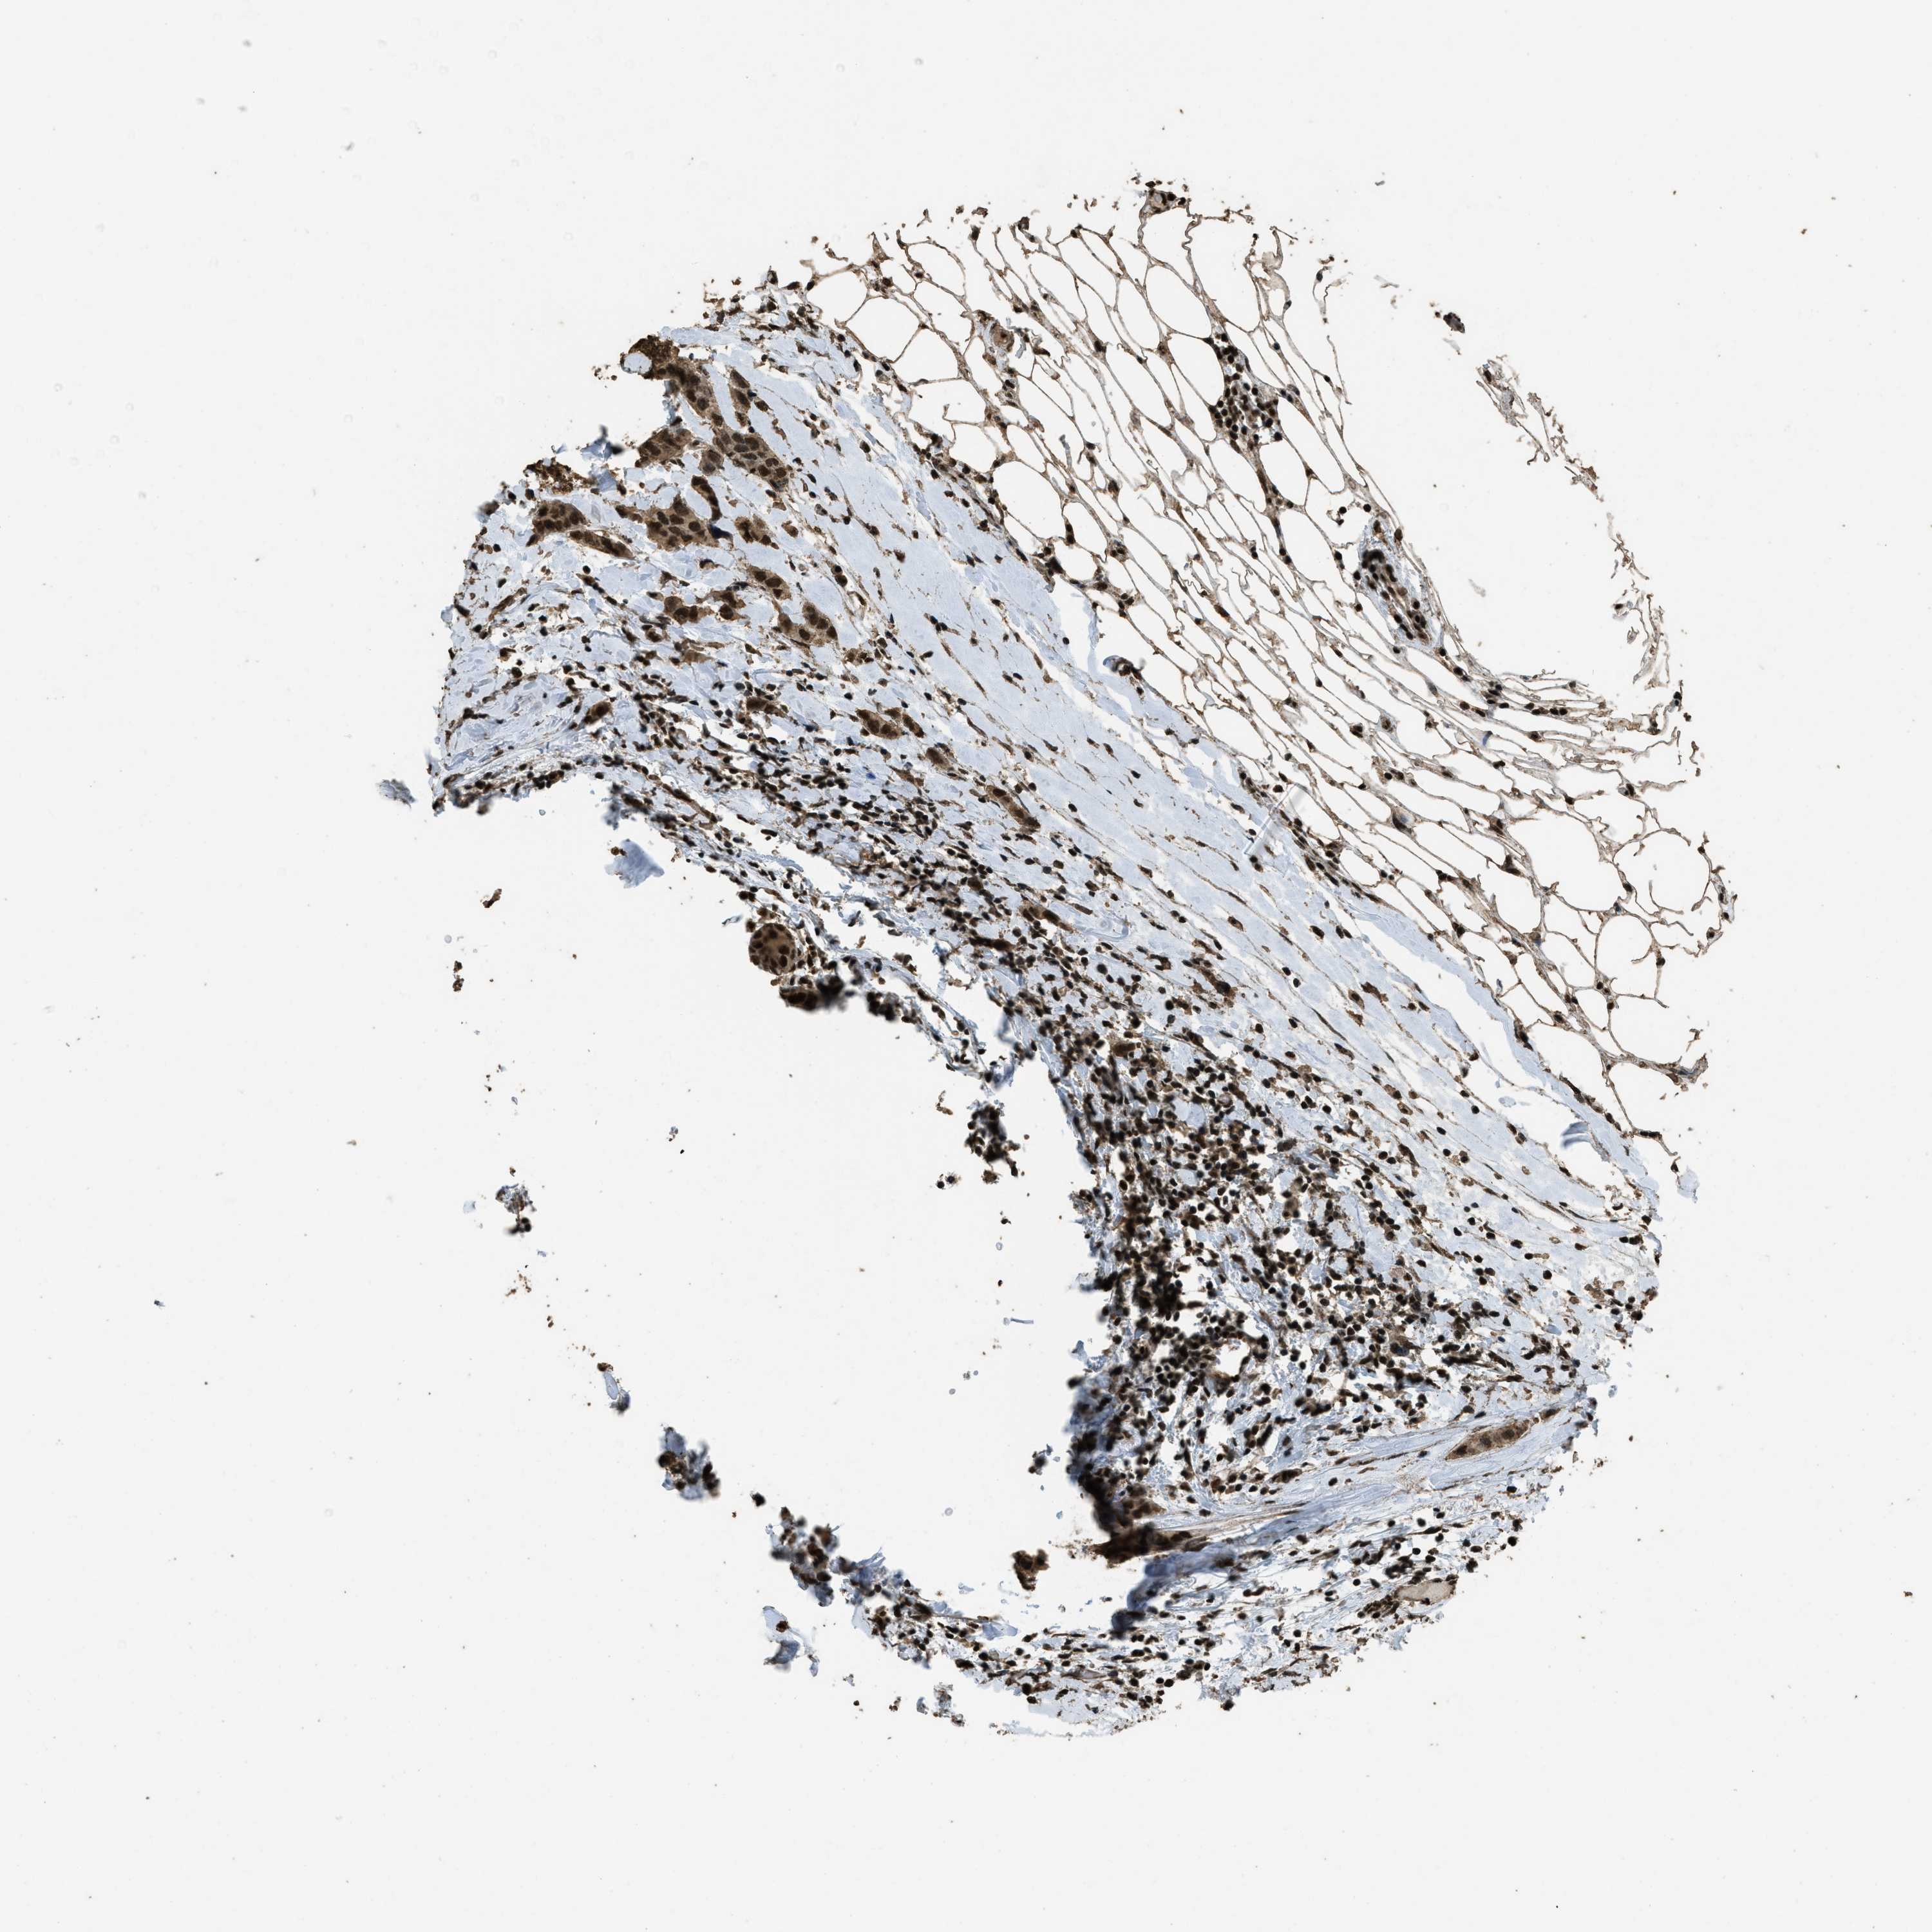

CANCER BREAST CANCER Show tissue menu

BRCA TCGA BRCA VALIDATION PROTEIN EXPRESSION